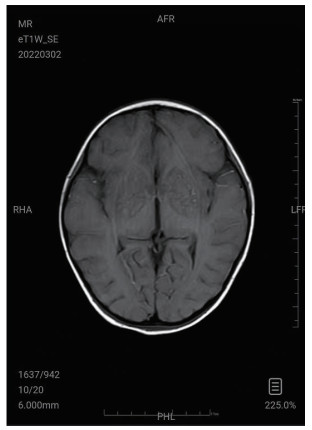

| 图 3 3月2日颅脑MRI |

图 1为颅内弥漫脑实质肿胀,脑沟脑回显示不清,脑室受压,部分脑沟内可见高密度影,右侧小脑幕密度增高。中线结构居中。副鼻窦内见软组织密度影。图 2为大脑皮层、小脑及脑干形态肿胀,呈稍长T2信号影,有类似束带征。图 3为后颅窝去骨辨减压+小脑部分切除术后复查: 脑疝征象明显好转。